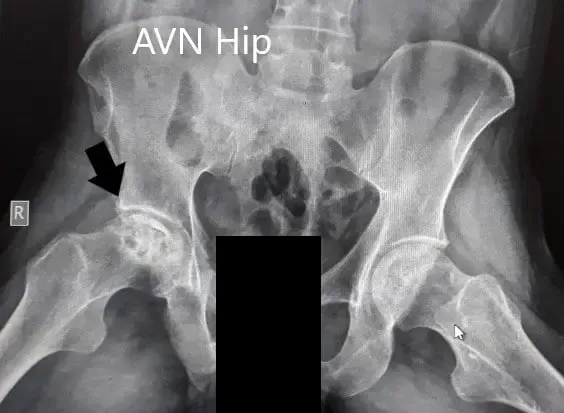

Se obtuvieron imágenes en forma de radiografías que sugirieron el colapso de la cabeza femoral en el lado derecho. Hubo una pérdida de esfericidad de la cadera derecha con esclerosis y quistes subcondrales. La cadera izquierda tenía un contorno intacto. Se recomendó la resonancia de pelvis en ambas caderas.

Radiografía preoperatoria de la pelvis con ambas caderas en vistas anteroposterior y lateral con patas de rana